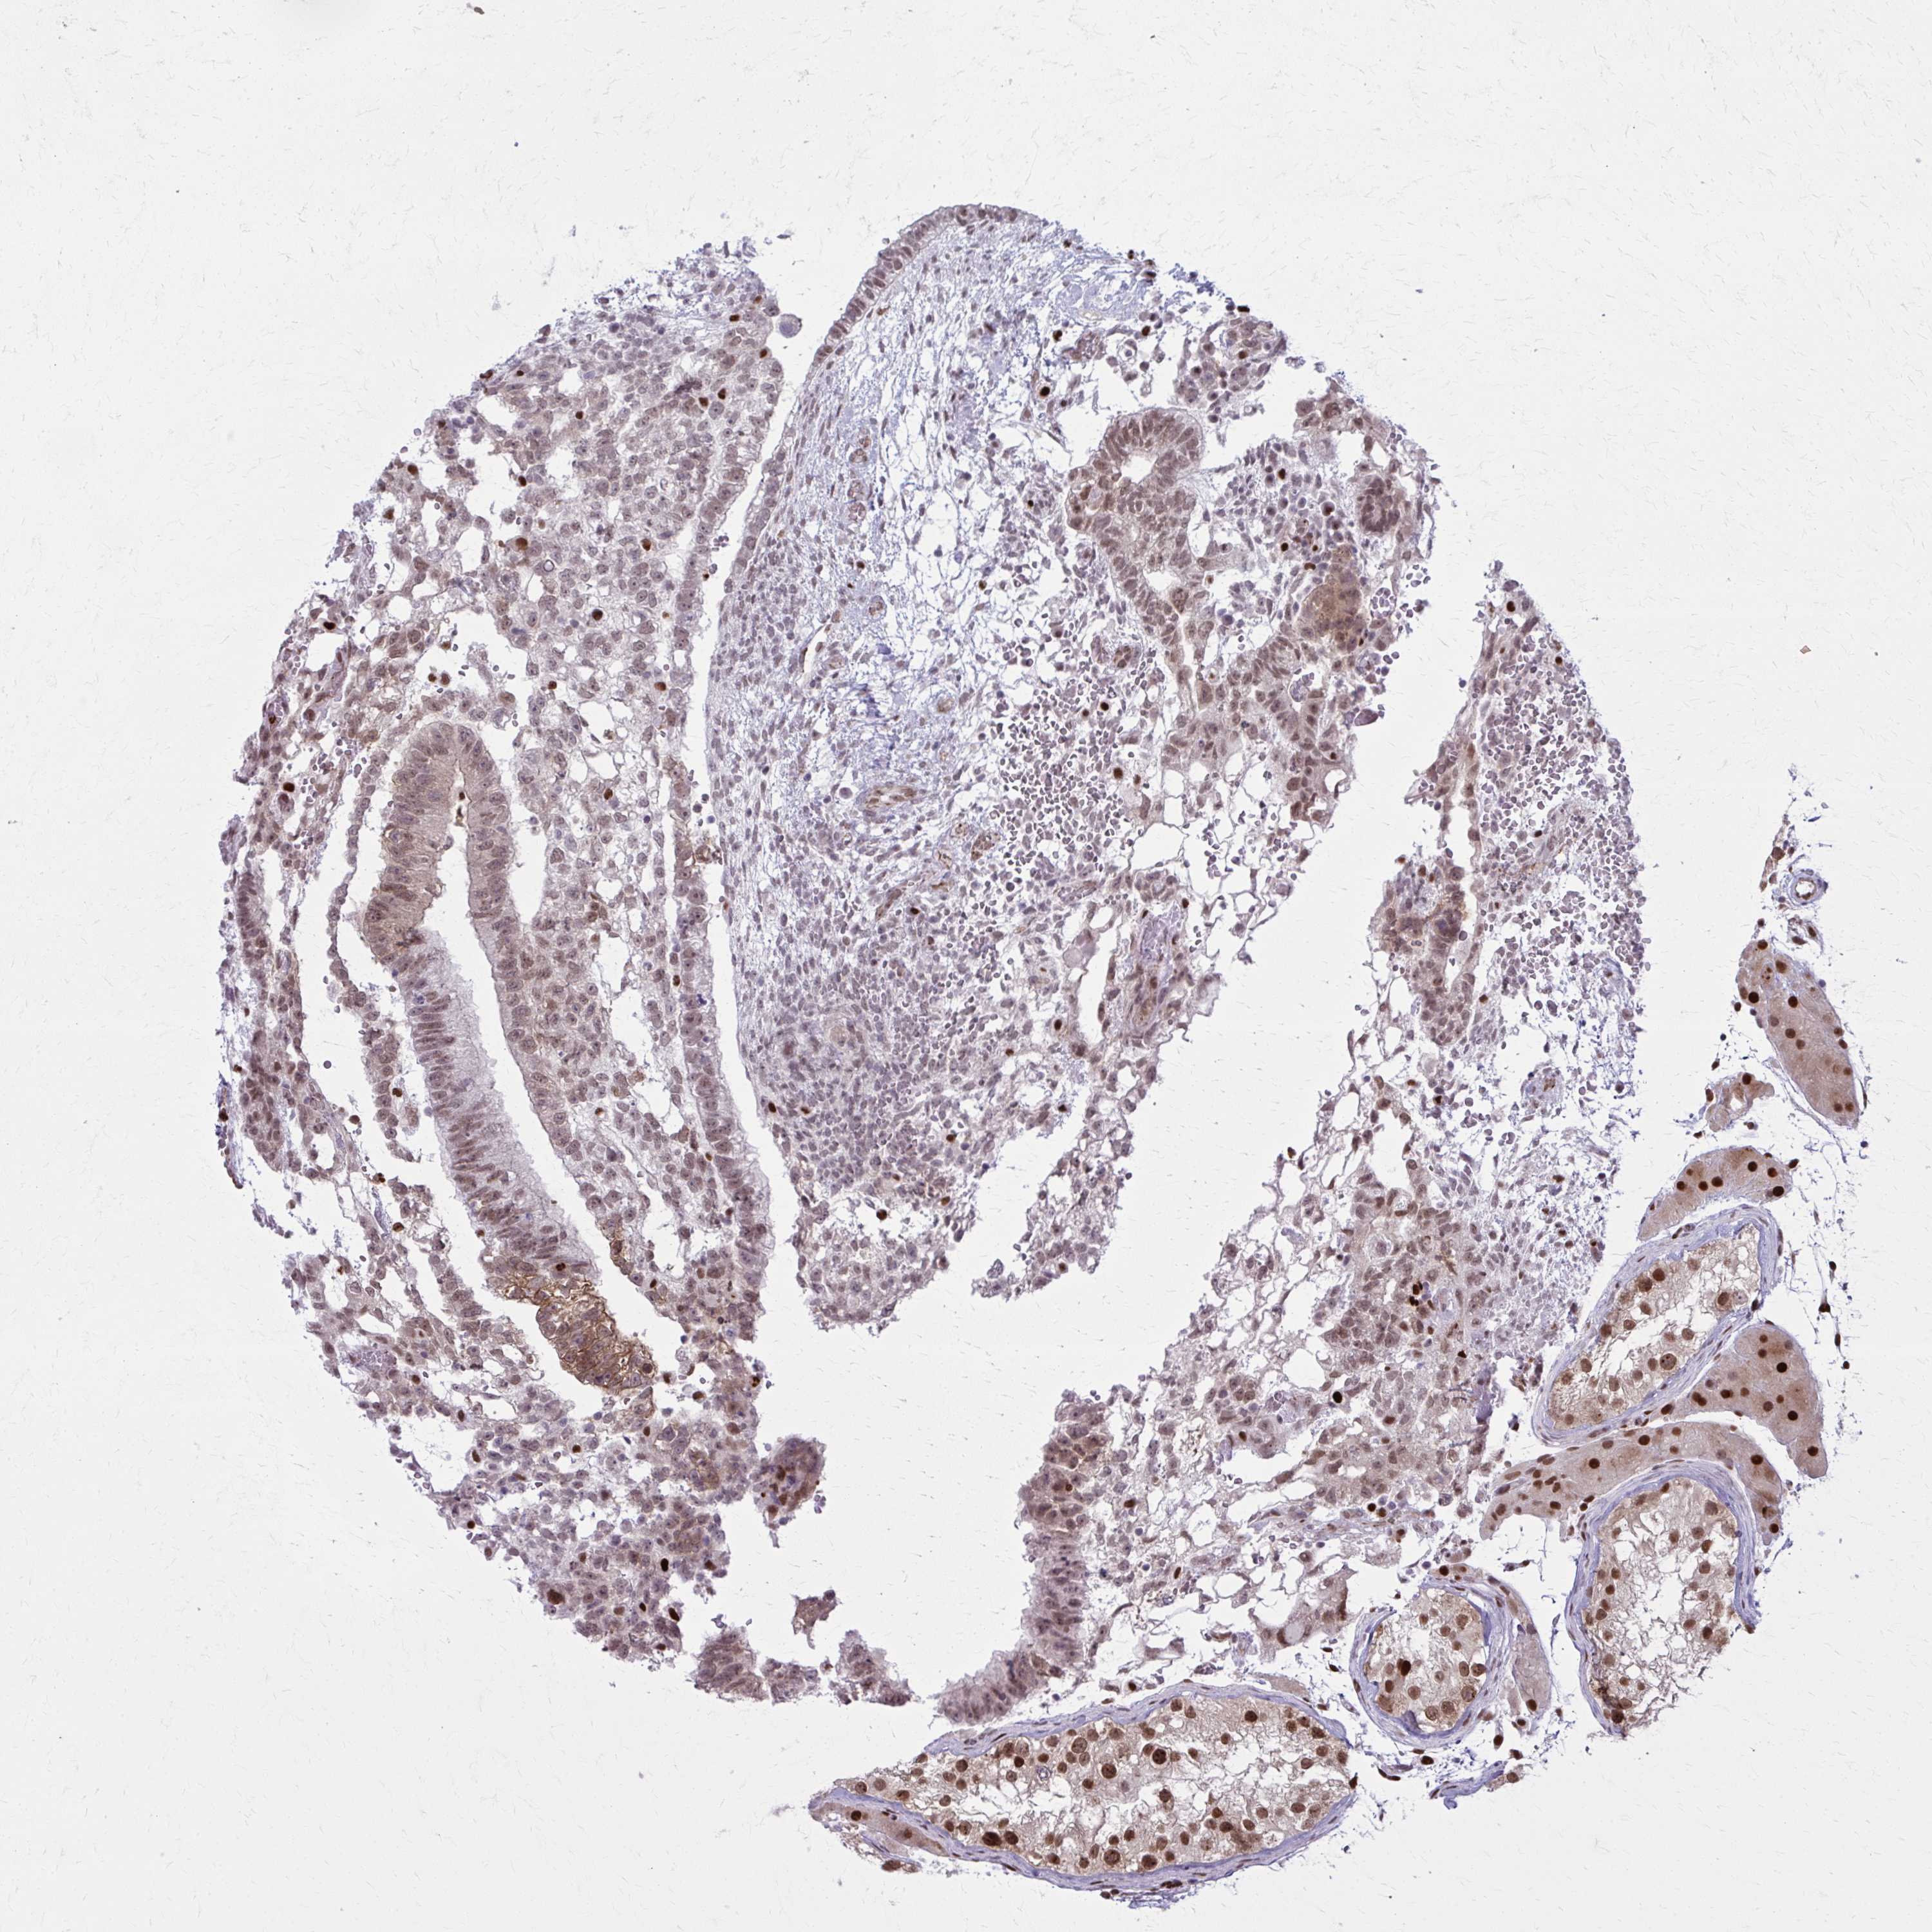

TESTIS CANCER - Protein expressioni

A mouse-over function shows sample information and annotation data. Click on an image to view it in a full screen mode. Samples can be filtered based on level of antibody staining by selecting one or several of the following categories: high, medium, low and not detected. The assay and annotation is described here.

Note that samples used for immunohistochemistry by the Human Protein Atlas do not correspond to samples in the TCGA dataset.

Antibody stainingi

Antibody staining in the annotated cell types in the current human tissue is reported as not detected, low, medium, or high, based on conventional immunohistochemistry profiling in selected tissues. This score is based on the combination of the staining intensity and fraction of stained cells.

Each image is clickable and will lead to virtual microscopy that enables deeper exploration of all samples and also displays staining intensity scores, fraction scores and subcellular localization as well as patient and tissue information for each sample.

Antibody HPA059632

Staining

High

Medium

Low

Not detected

Intensity

Strong

Moderate

Weak

Negative

Quantity

>75%

75%-25%

<25%

None

Location

Nuclear

Cytoplasmic/membranous

Cytoplasmic/membranous,nuclear

Carcinoma, Embryonal, NOS

Seminoma, NOS

Teratoma, malignant, NOS